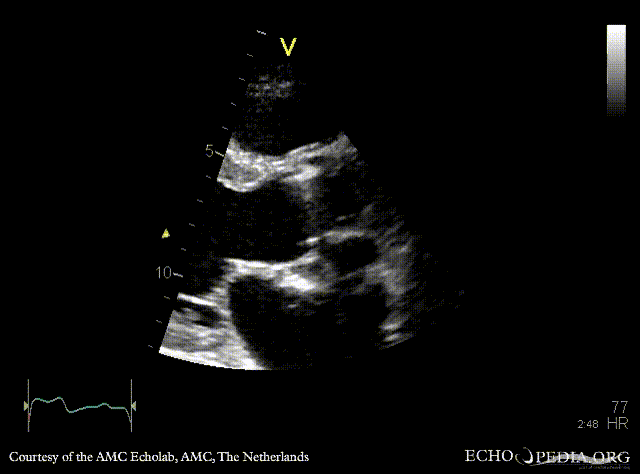

E00846.gif E00847.gif

PSAX: abscess of aortic valve prosthesis A4CH with Color Doppler: flow from abscess into the left atrium, severe mitral regurgitation